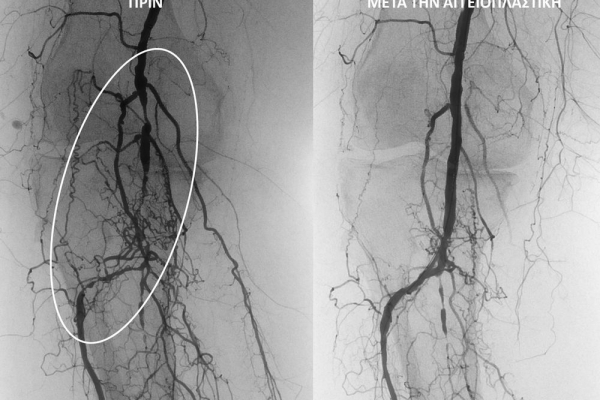

O σακχαρώδης διαβήτης είναι μεταβολική ασθένεια η οποία χαρακτηρίζεται από αύξηση της συγκέντρωσης του σακχάρου στο αίμα (υπεργλυκαιμία) και διαταραχή του μεταβολισμού της γλυκόζης. Ο βαθμός αύξησης της γλυκόζης στο αίμα και η παραμονή των αυξημένων τιμών της για μεγάλο χρονικό διάστημα βλάπτουν, κυρίως, τα μικρά αγγεία, προκαλώντας διαβητική νευροπάθεια, διαβητική νεφροπάθεια, αμφιβληστροειδοπάθεια κ.τ.λ., με σοβαρότατες συνέπειες σε πολλά όργανα-συστήματα.Στην Ελλάδα κάθε χρόνο πραγματοποιούνται 2.000 – 3.000 ακρωτηριασμοί κάτω άκρων, αφού το 4-5% των πασχόντων από διαβήτη εμφανίζει περιφερική αγγειοπάθεια με έλκη ή και γάγγραινα στα πόδια. Σε ποσοστό 80% οι ακρωτηριασμοί θα μπορούσαν να αποφευχθούν και η επεμβατική ακτινολογία μπορεί να βοηθήσει σημαντικά.Η διαδερμική ενδαγγειακή αγγειοπλαστική (percutaneous transluminal angioplasty, PTA) είναι μια ελάχιστα επεμβατική μέθοδος αντιμετώπισης των αρτηριακών στενώσεων ή και αποφράξεων του διαβητικού ποδιού (περιφερικήδιαβητικήαρτηριοπάθεια).